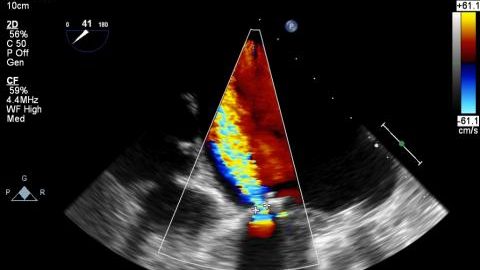

Echocardiography

Echocardiography is the use of ultrasound waves to investigate the actions of the heart. An echocardiogram, sometimes called an echo, uses Read More